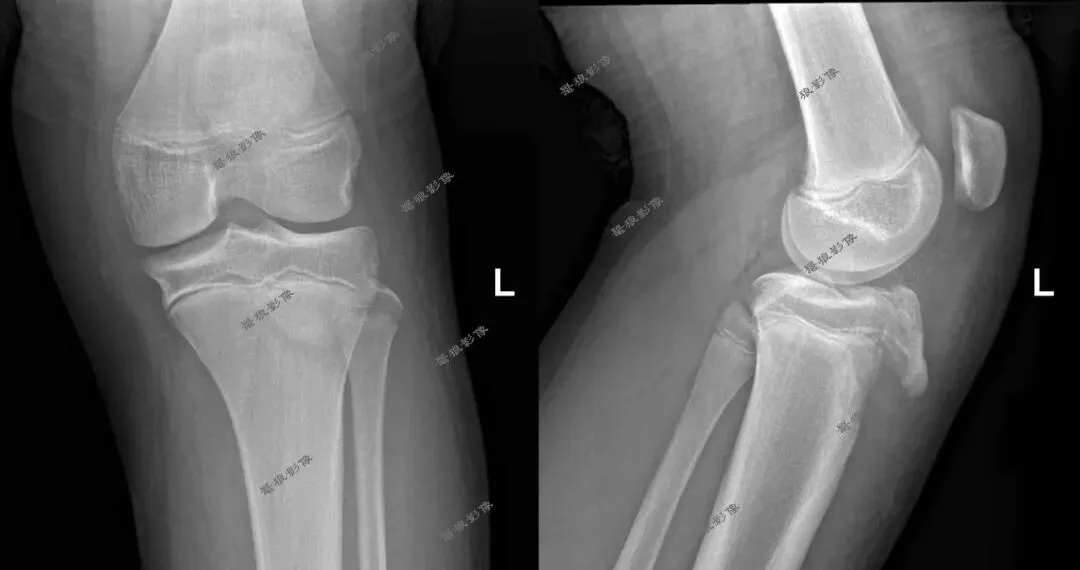

M,11y。

缘患者入院3小时余前运动后出现左膝部疼痛,活动受限,当时无昏迷,遂送至急诊就诊,查X片:左胫骨结节骺离骨折。

一.术前X线片

二.术前CT

胫骨结节骨折(OgdenIIIA型 )